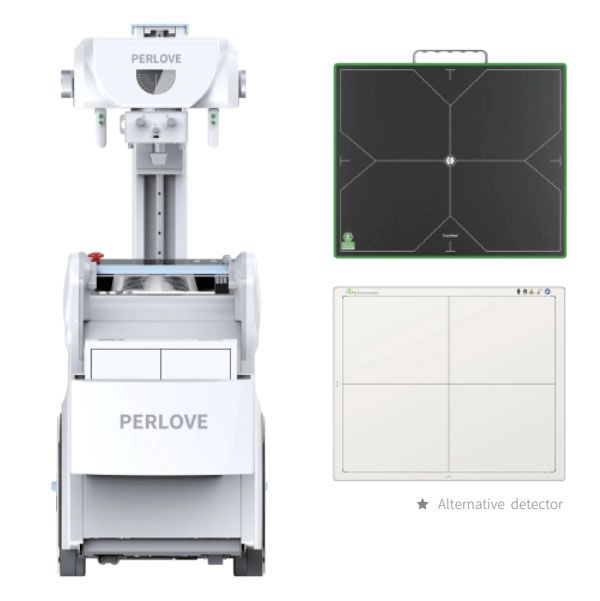

• Excellent wireless detector: PLX5200A 50kW version adopts 14*17 inches wireless detector, which has wide field of vision and convenient positioning;with high image clarity and fine imaging.The l6 bit gray scale can clearly show the radiation position tissue details of the exposure site, with high image differentiation and accurate clinical diagnosis.

Integrated workstation:

• The integrated workstation integrates the image acquisition system and theX-ray generator control system, which is convenient and quick to operate.

• The image acquisition system has multiple functions such as patient management,image acquisition, image processing, image observation,and case reports.

• The workstation supports the DICOM3.0 standard protocol and can transfer images with PACS system.

• Built-in preset parameters for standardized postures, graphical display of a variety of commonly used clinical postures, support for re-editing and memorizing posture parameters, therefore doctors can adjust and optimize exposure parameters personally.

Graphical operation interface:

• Large-size LCD touch screen, equipped with professional image processing software with humanized graphical interactive interface which can shorten therunning-in period between medical staff and the machine effectively.

• Understandable icons, simple and easy to understand, save training time and cost for medical treatment.